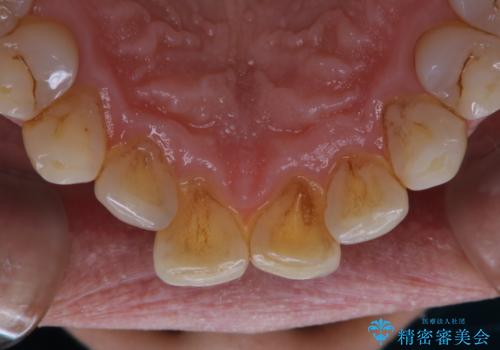

- インビザラインでの矯正治療中の方です。コーヒーをよく飲むため、着色が気になるとのことでした。PMTC60分コースを行いました。

PMTC(保険外治療)は、毎日の歯磨きで落としきれない汚れや、コーヒ、紅茶・タバコのヤニなどの着色も除去します。目には見えない歯と歯の間・歯肉の境目・インビザライン中はアタッチメント周囲などに残っているプラーク(歯垢)もしっかり取り除きます。PMTCでは専門的な機械や材料を使用して、徹底的に汚れを除去するため、虫歯・歯周病・口臭予防などにつながります。